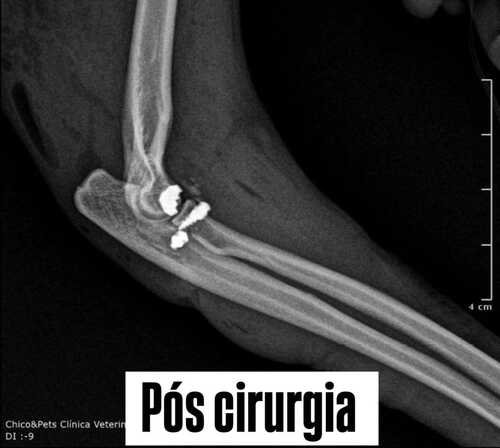

Levamos ela imediatamente ao veterinário, e a situação exigiu cirurgia urgente no cotovelo, que não podia esperar. A cirurgia foi realizada com sucesso, mas o custo total ficou em R$ 4.500, um valor alto para nós no momento. Como a operação não podia ser adiada, conseguimos esse dinheiro emprestado, e agora precisamos devolver esse valor.